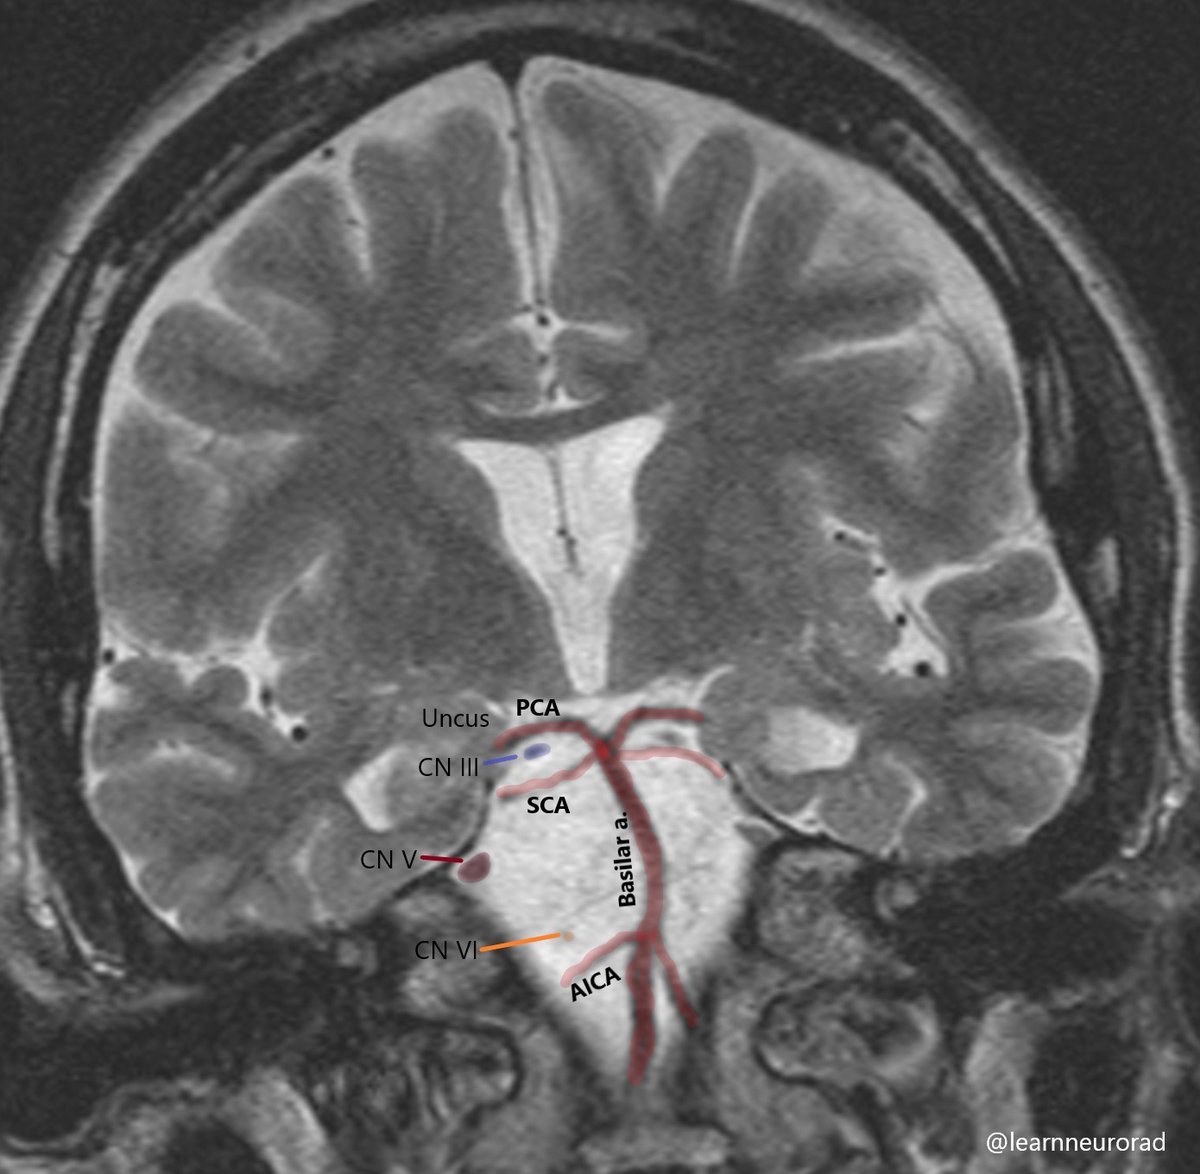

Cranial nerve anatomy to help understand why uncal herniation and Pcomm aneurysms result in a fixed and dilated pupil. CN III and IV run b/w the PCA & SCA. CN V and VI run in the prepontine cistern, lateral to the basilar artery. #Neurorad #radres #Neurotwitter #MedEd #MedTwitter